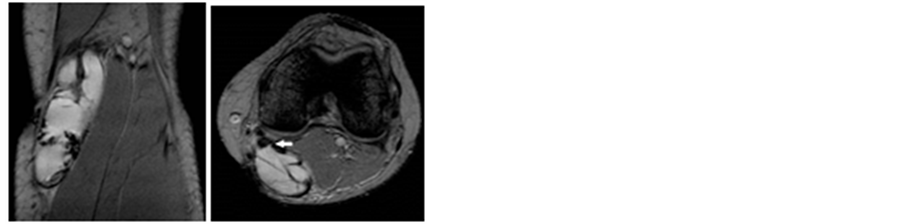

Synovial sarcoma accounts for approximately 10% of soft tissue sarcomas. Men and women are affected equally and the mean age of presentation is 32. They occur most often in the extremities, with 70% of all cases occurring in the lower limbs. These masses are generally slow growing and patients seek medical attention, a mean of 2.5 years after initiation of symptoms. Synovial sarcoma is thought to originate from primitive mesenchymal cells that after differentiation resemble synovial cells. Synovial sarcomas do not commonly arise in intra-articular locations but rather near them. They have a 50% recurrence rate within two years and they metastasize mainly to the lung [8] . On MRI, lesions are typically found to be greater than 5 cm, near a joint, and adjacent to bone. T2 weighted images, Figure 3, often display areas that are low, iso-, and hyper-intense to fat (“triple sign”) [9] . Smaller lesions may be found more peripherally, have smoother contours, have uniform signal characteristics, and lack local invasion.

Figure 3. Synovial sarcoma. (a) T2 fat sat sagittal; (b) T2 fat sat sagittal; (c) T2 fat sat Axial sequences.